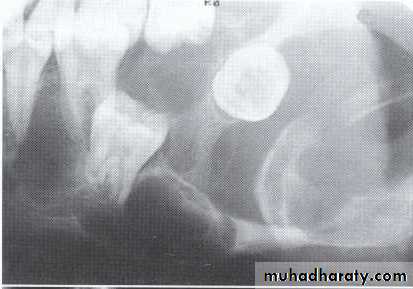

A: Odontogenic fibroma

B,C,D:Odontogenic myxoma.Odontogenic Adenomatoid Tumor (OAT)

The maxillary left canine and premolar have been displaced superiorly by the tumor.

The canine and lateral incisor have been displaced by the lesion.Soap bubble-like radiolucencies